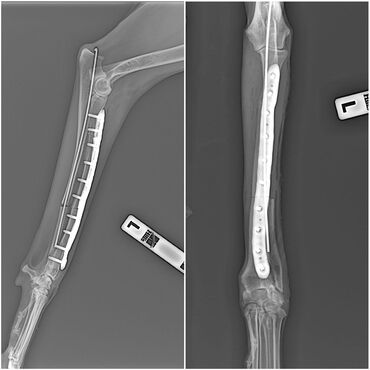

Ветеринар все услуги ветеринарного врача лечение до полного

Ветеринар все услуги ветеринарного врача лечение до полного выздоровления кастрация УЗИ лошадей и крс стерелизация купирование осмотр консультация бесплатная